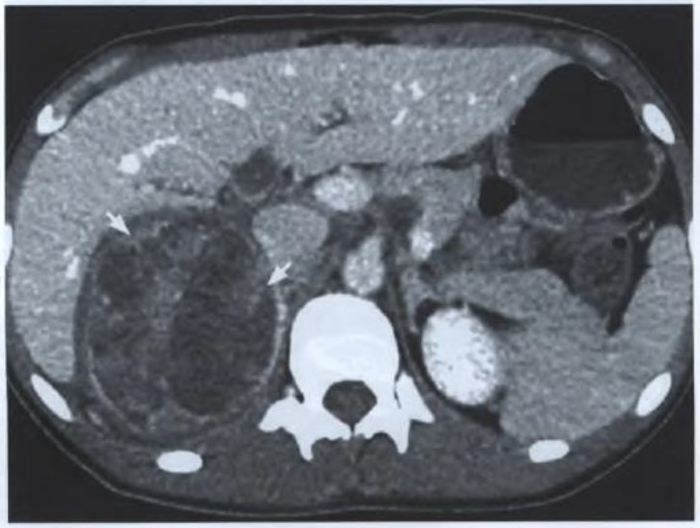

Mulher de 45 anos, apresentando sinais de virilização, procura atendimento endocrinológico e, na primeira consulta, alguns exames laboratoriais e de imagem são solicitados. O ultrassom de rotina, realizado semanas antes da referida consulta, descreve massa na adrenal direita e sugere prosseguimento da investigação. O endocrinologista solicita tomografia abdominal com contraste. De acordo com a imagem tomográfica mostrada a seguir, extraída da tomografia da paciente do caso relatado, assinale a alternativa INCORRETA.